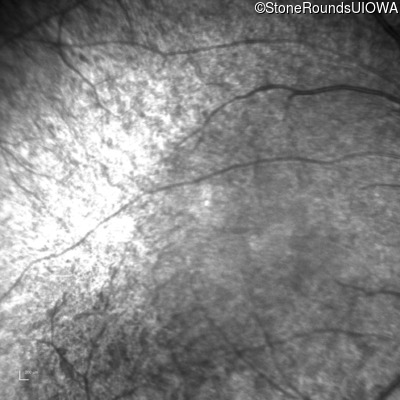

Age at visit: 15 years

This 15 year old male has had very poor vision and nystagmus since the first year of life.

Diagnosis & molecular findings

Senior-Loken Syndrome IQCB1 Phe141 del2cacTT Phe141 del2cacTT AR